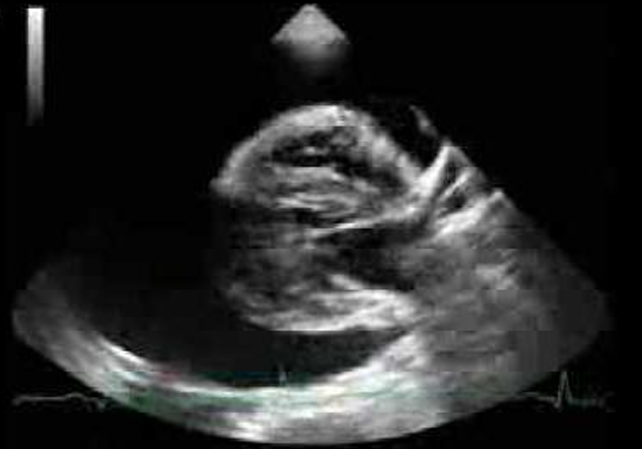

Echocardiography

• 혈액 흐름, 와류 등 확인해야 함.

• Turbulent doppler flow parttern

• 폐고혈압 측정